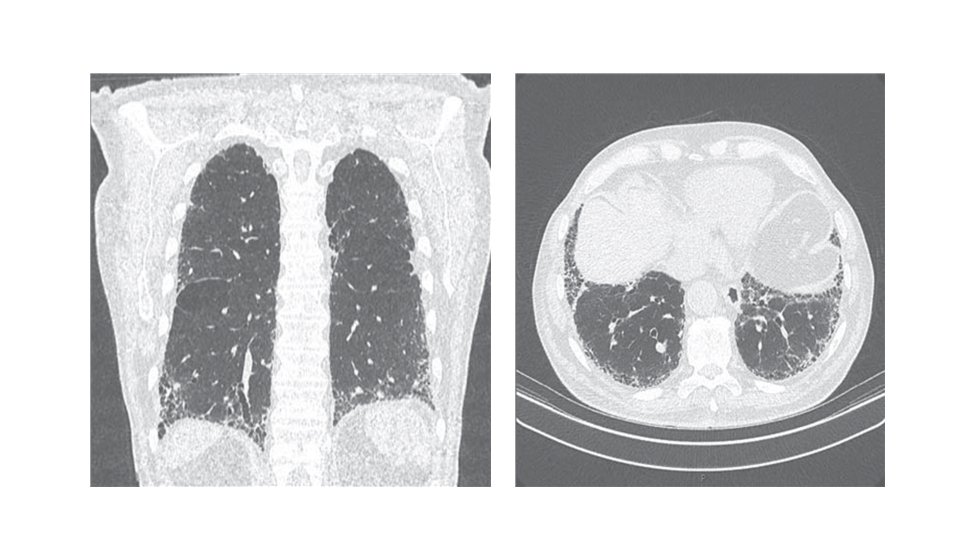

Symptoms & signs: persistent dry cough, insidious and progressive shortness of breath, inspiratory crackles & digital clubbing. Radiology: CXR- small lung volume, reticulonodular shadowing. High-resolution CT- (the diagnostic test of choice) showing ground-glass appearances, reticulonodular shadowing, honeycomb cyst & traction bronchiectasis. Pulmonary function test: restrictive ventilatory defect, reduced lung volume & decrease gas exchange.

Investigations: A/ CXR: bilateral lower lobe and subpleural reticular shadowing but can be normal in early or limited disease. B/ High-Resolution CT of the chest (HRCT): patchy, predominantly peripheral, subpleural and basal reticular shadows. Honeycombing cysts and traction bronchiectasis in advanced disease. • It can be useful to exclude other differential diagnoses such as hypersensitivity pneumonitis, sarcoidosis and asbestosis